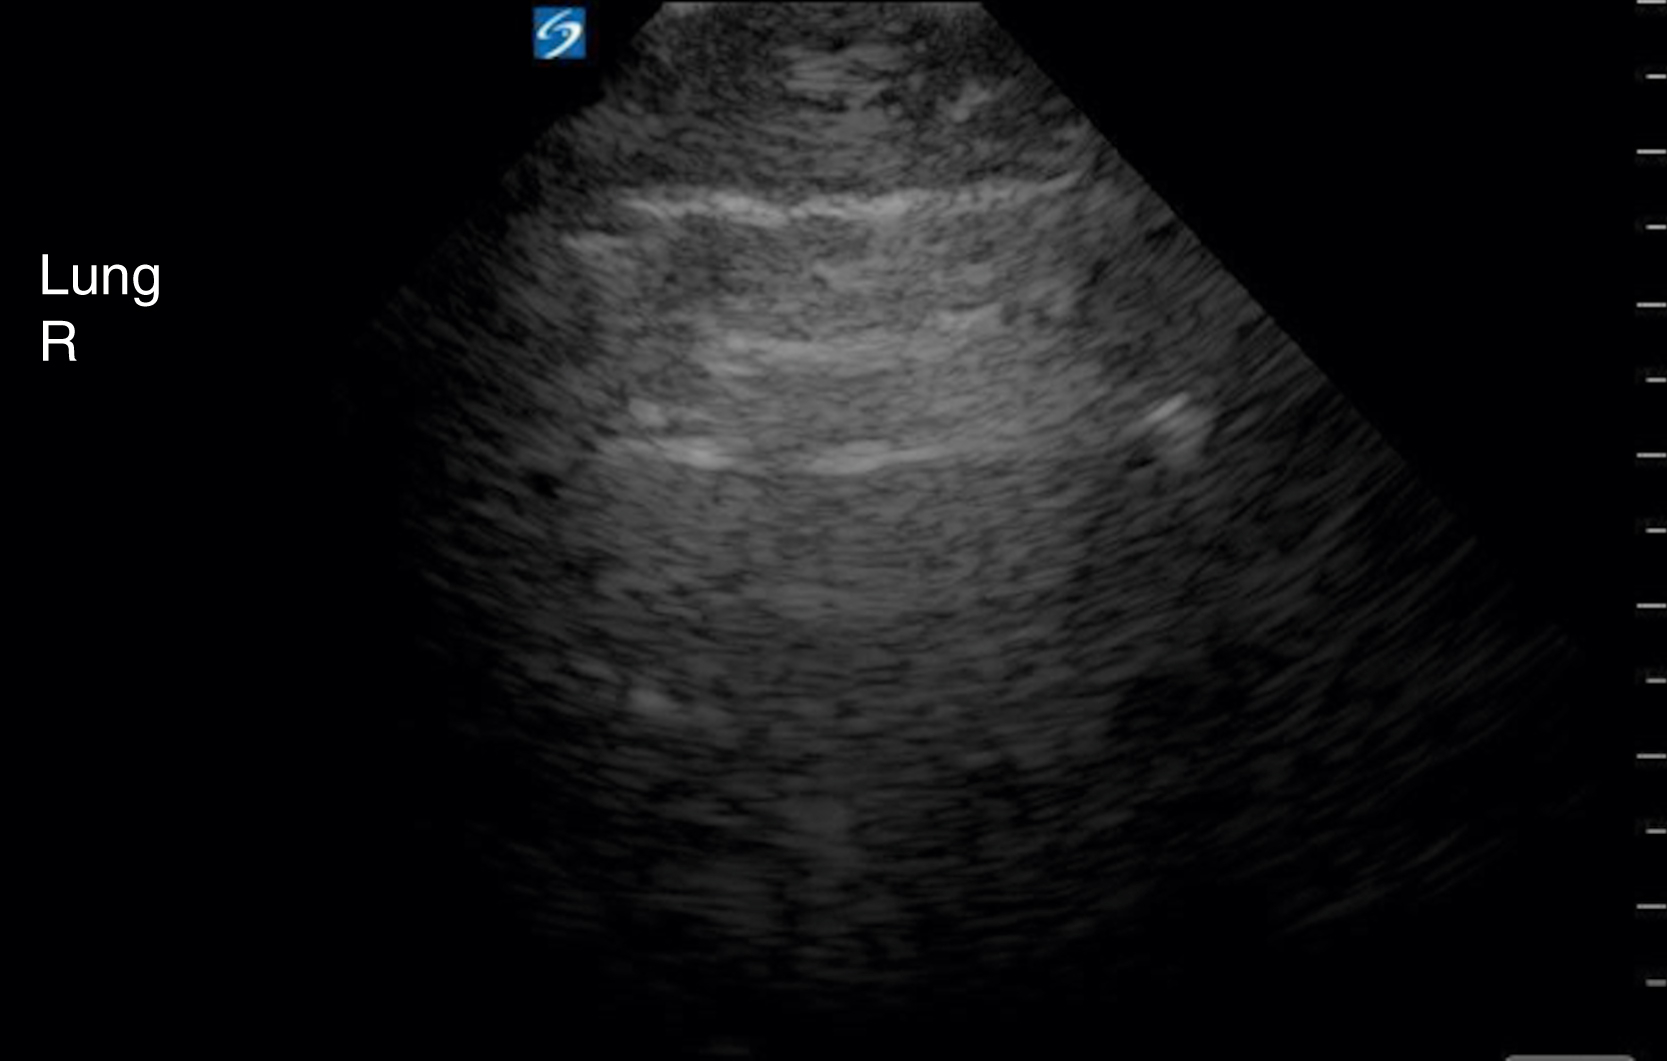

The visualization of lung sliding excludes the presence of a pneumothorax at that location on the patient’s chest wall. Although M-mode and color Doppler techniques have been described as adjuncts to the evaluation of patients with suspected pneumothorax, neither is a necessary component of the examination. Absent lung sliding can result from a variety of causes in addition to pneumothorax, including pleural adhesions or consolidations, blebs, pleurodesis, partial or complete pneumonectomy, and contralateral mainstem bronchus intubation ( Fig. e3.15 ). A lung point sign is identified at the border of the pneumothorax, where the image shows absent lung sliding until the lung moves into the interspace with respiration ( Video e3.12 ).

M mode images of the lung. (A) Normal lung with “seashore” sign. (B) Pneumothorax with “stratosphere” or “barcode” sign.

Once the pleural line has been evaluated for sliding, then the determination of intraparenchymal fluid should be made. A lines indicate a dry lung, whereas B lines indicate the presence of fluid within the lung. B lines are vertical hyperechoic reverberation artifacts that arise from the pleura, move with respiration, extend off the screen without fading, and erase the normal A line pattern ( Fig. e3.16 ). Normally found in small numbers in the dependent areas of the lung (atelectasis), the widespread distribution of B lines, typically 3 or more in one lung window, indicates increased interstitial and/or alveolar thickening due to fluid accumulation (edema) or scarring (fibrosis). , As the lung accumulates fluid with consolidation, such as a lobar pneumonia, it can appear echogenic, so-called liver-like (hepatization). When diagnosing pneumonia with lung US, the consolidation needs to be in contact with the pleura to be visible within an intercostal window. Other signs can be seen with pneumonia, but dynamic air bronchograms, hyperechoic areas within bronchi that move with respiration, usually within the consolidated lung, are highly specific for alveolar consolidation. As seen in the E-FAST examination, pleural fluid appears as an anechoic collection above the diaphragm, although internal echoes may be present in cases of chronic, infected, or loculated effusions.